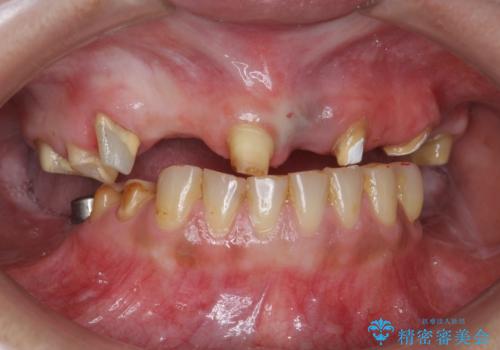

痛くて噛めない インプラントで全て治療したい

- 痛くて噛めない、これまでだましだまし治療をしてきたがこれを機にすべてきっちりと治したい、口の中の悩みを解決したいと来院されました。

抜歯や歯周病治療、欠損補綴を含め、全顎的な治療を計画・提案します。

(他Drからの引き継ぎ [治療中] の状態より担当)